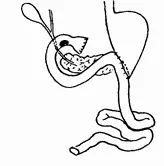

Еще чаще стали образовываться пептические язвы соустий после полного выключения привратника путем перерезки антрального отдела по Эйзельсбергу (рис. 8). Эти операции ознаменовались таким количеством пептических язв соустья, что подобные вмешательства уже давно всеми оставлены.

Рис. 8.Выключение по Эйзельсбергу, пептическая язва в 50%